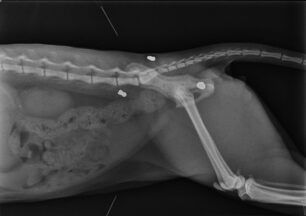

Μια αδέσποτη γάτα πυροβολημένη με αεροβόλο εντόπισε στις 3 Ιουνίου η Κυριακή Λυκουρέση την περιοχή του Περιστερίου Αττικής στη οδό Σουρή. Η γάτα μόλις εντοπίστηκε. Το ζώο σερνόταν και η κα Λυκουρέση αφού το έπιασε…διαβάστε περισσότερα